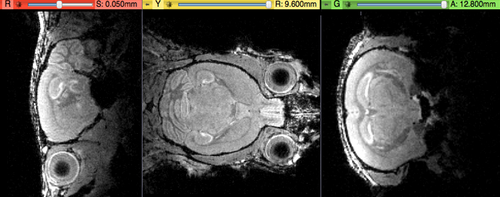

shown are, from left to right, panels of axial, sagittal and coronal views.

original, not registered

affine registered brains affine registered

registered brains after 5x5x5 nonrigid BSpline alignment